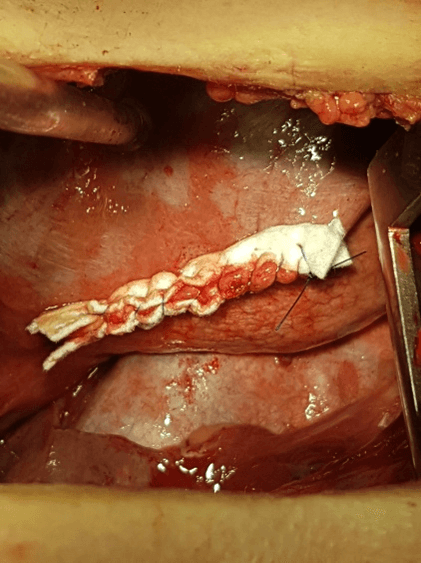

No recurrence has been mentioned 6 months after the completion of the hormone therapy. The fifth patient was operated on via a VATS bullectomy and pleurodesis, after two episodes of CP, which were managed with chest tube two years before. A flexible bronchoscopy was performed before the bullectomy because of incomplete expansion of the right lower lobe. Because of another episode of recurrent pneumothorax one year after the VATS procedure, the patient was operated on via a right posterolateral mini- thoracotomy. The findings were small fenestrations / holes on the central tendon of the diaphragm, which were not being discerned in the initial VATS (Figure 1). Suturing of the fenestrations with PTFE - pledget running suture was the final treatment (Figure 2). She also underwent hormone therapy for 6 months during postoperative period, in order to suppress menstruations. Postoperative hospital stay was 10 days. After a follow-up period of 1 year the outcomes were satisfactory for the last patient who didn’t display any symptom at the beginning of her menstrual cycles or radiological evidence of relapse.

Figure 2: Suturing of the fenestrations with PTFE - pledget running suture.